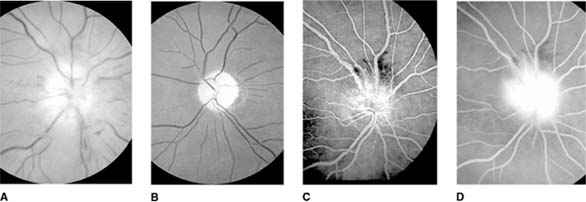

PAPILLEDEMA (Figures 14-9, 14-14, new window  14-15 and new window  14-16)

Figure 14-15

Figure 14-15: Chronic papilledema with prominent disk swelling, capillary dilation, and retinal folds but few hemorrhages or cotton-wool spots (A) and (B). Fluorescein angiography demonstrates the capillary dilation in its early phase (C) and marked disk leakage in its late phase (D).

For papilledema to occur, the subarachnoid spaces around the optic nerve must be patent and connect the retrolaminar optic nerve through the bony optic canal to the intracranial subarachnoid space, thus allowing increased intracranial pressure to be transmitted to the retrolaminar optic nerve. There slow and fast axonal transport is blocked, and axonal distention, particularly noticeable at the superior and inferior poles of the optic disk, occurs as the first sign of papilledema. Hyperemia of the disk, dilated surface capillary telangiectases, blurring of the peripapillary disk margin, and loss of spontaneous venous pulsations are the signs of mild papilledema. Edema around the disk can cause a decreased sensitivity to small isopters on visual field testing, but circumferential retinal folds with changes in the internal limiting membrane reflexes (Paton's lines) will eventually become evident as the retina is pushed away from the choked disk; when the retina is pushed away, the blind spot will be enlarged to large isopters on visual field testing as well. In acute papilledema, probably as a consequence either of markedly elevated or rapidly increasing intracranial pressure, there are hemorrhages and cotton-wool spots, indicating vascular and axonal decompensation with the attendant risk of acute optic nerve damage and visual field defects (Figure 14-14). There may also be peripapillary edema (which can extend to the macula) and choroidal folds. In chronic papilledema (Figure 14-15), which is likely to be the consequence of prolonged moderately raised intracranial pressure, a process of compensation appears to limit the optic disk changes such that there are few if any hemorrhages or cotton-wool spots. With persistent raised intracranial pressure, the hyperemic elevated disk gradually becomes gray-white as a result of astrocytic gliosis and neural atrophy with secondary constriction of retinal blood vessels, thus leading to the stage of atrophic papilledema (Figure 14-16). There may also be retinochoroidal collaterals (previously known as opticociliary shunts) linking the central retinal vein and the peripapillary choroidal veins, which develop when the retinal venous circulation is obstructed in the prelaminar region of the optic nerve. (Other causes of retinochoroidal collaterals are central retinal vein occlusion, optic nerve sheath meningioma, optic nerve glioma, and optic nerve head drusen.) Vintage papilledema is characterized by the presence of drusen-like deposits within the swollen optic nerve head.